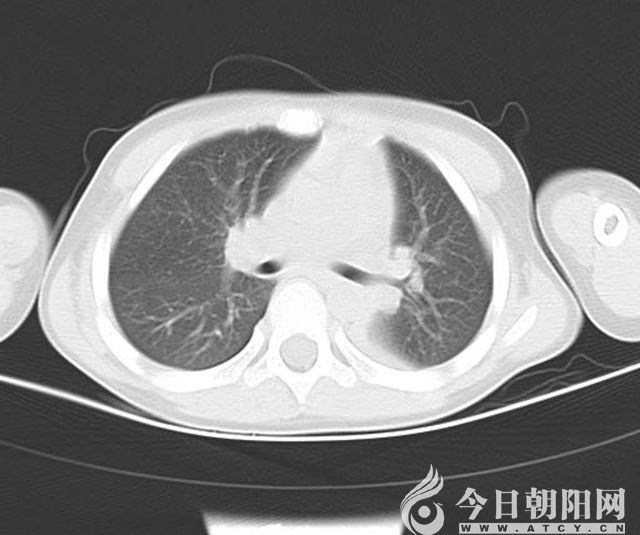

出院10天后復(fù)查肺CT

7月5日,一名4歲大的男孩兒,因“發(fā)熱7天,咳嗽3天”來到朝陽市第二醫(yī)院兒科就診。入院時,患兒精神狀態(tài)差,呻吟,無鼻翼扇動,可見輕度三凹征,左肺呼吸音較右側(cè)減弱;肺CT顯示左肺炎性病變,左肺下葉膨脹不良。通過檢查,診斷為重癥肺炎、胸腔積液、膿毒血癥、支原體感染,給予4代抗生素抗感染及抗支原體治療。住院第5天,復(fù)查肺CT顯示左肺下葉膨脹不良無明顯改善,考慮存在痰栓堵塞,立即進行纖維支氣管鏡檢查+支氣管肺泡灌洗術(shù)治療,灌洗過程中吸出塑形性痰栓多量。術(shù)后第6天復(fù)査肺CT,左肺上葉片影消失,左肺下葉膨脹不良明顯改善。7月19日,患兒出院。7月末,男孩兒來到醫(yī)院復(fù)査,肺CT顯示炎癥基本吸收。